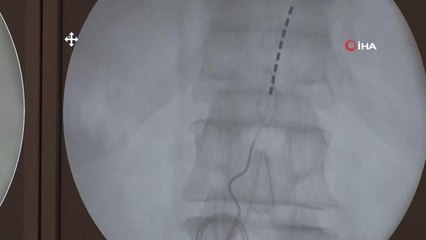

Uyurken nefesi 58 kez duran İbrahim Örer, 17 yıldır yaşadığı uyku apnesi sorununa dil kökü pili ameliyatıyla çözüm buldu. br br Florance Nightingale Hastanesi'nde 1,5 saat süren operasyonla İbrahim Örer, dil kökü pili sayesinde kesintisiz solunum ve sağlıklı bir uykuya kavuştu.